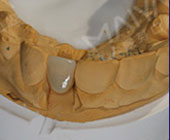

缺牙6个月,我想要回我的牙齿!

手术成功原理:针对缺牙引起牙槽骨萎缩吸收的情况,通过GPR植骨和保持位点手术形成新的牙槽骨。再通过数字化种牙完成前牙美学区的植入,实现即刻负重,拥有良好的美学效果… [详细]

前牙美学度高

植体结合稳固